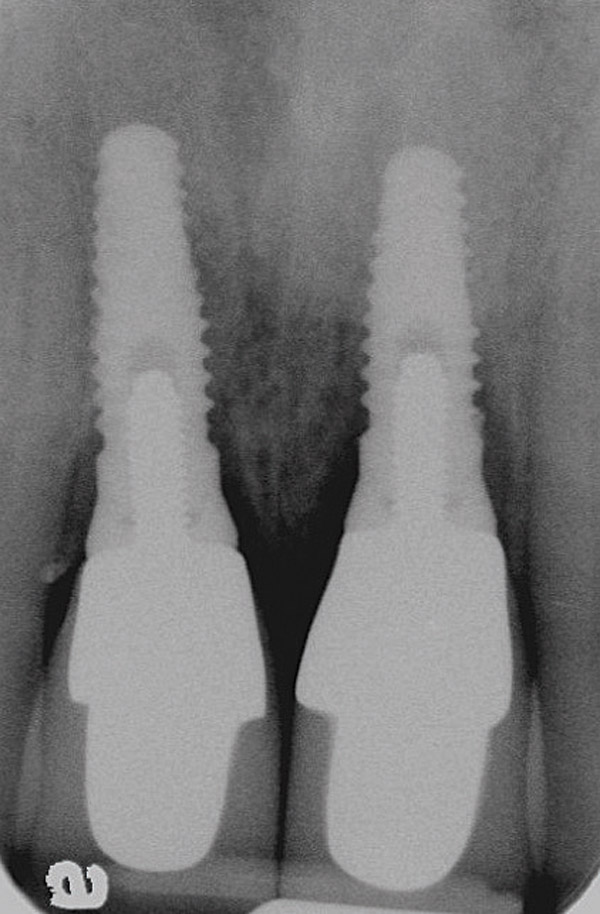

Figure 18  Periapical radiographs of the final implants show good bone levels and interproximal spacing between the implants and adjacent teeth.

Figure 18